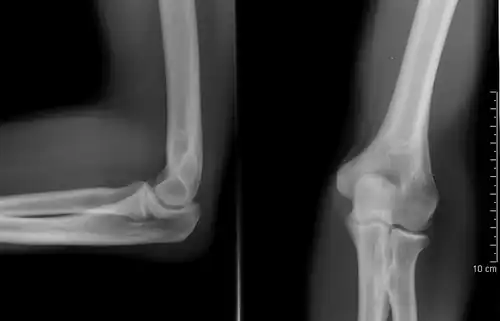

A plain radiograph of the elbow

The creation of images by exposing an object to X-rays or other high-energy forms of electromagnetic radiation and capturing the resulting remnant beam (or "shadow") as a latent image is known as "projection radiography". The "shadow" may be converted to light using a fluorescent screen, which is then captured on photographic film, it may be captured by a phosphor screen to be "read" later by a laser (CR), or it may directly activate a matrix of solid-state detectors (DR—similar to a very large version of a CCD in a digital camera). Bone and some organs (such as lungs) especially lend themselves to projection radiography. It is a relatively low-cost investigation with a high diagnostic yield. The difference between soft and hard body parts stems mostly from the fact that carbon has a very low X-ray cross section compared to calcium.